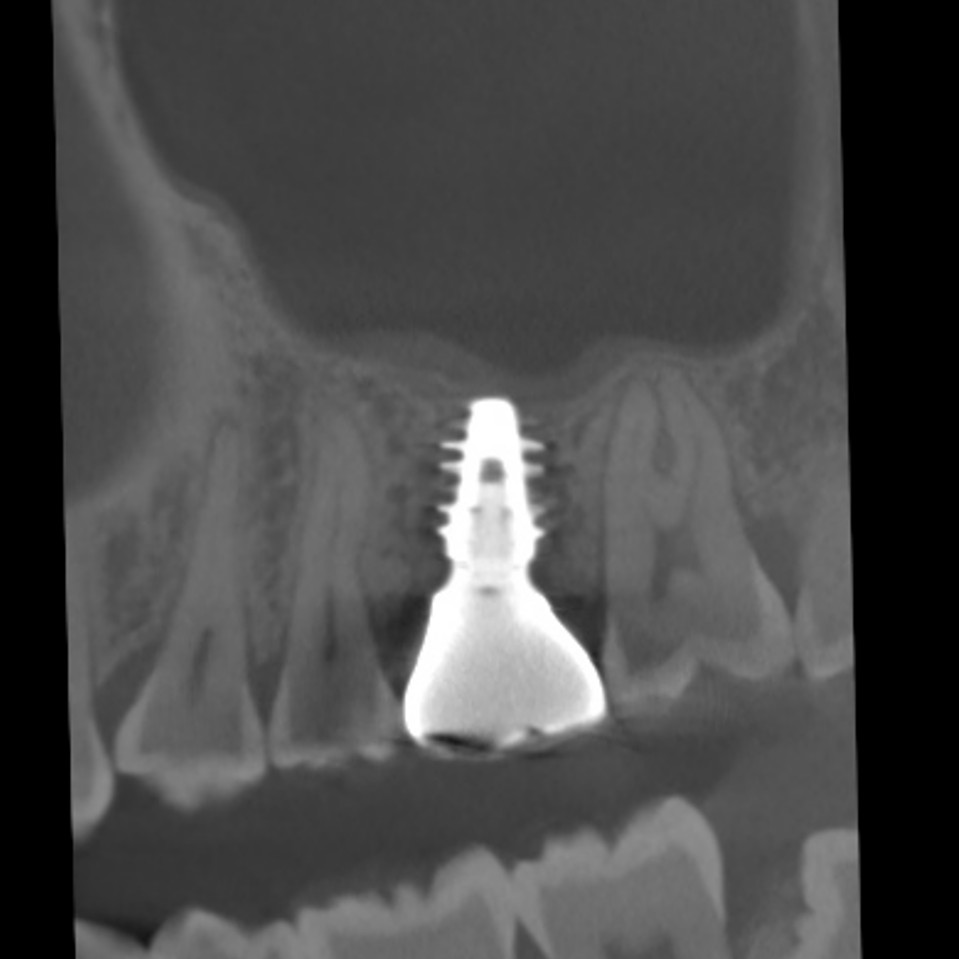

上の奥歯は上顎洞までの距離が短くインプラントが難しいことも多いのですが、即時埋入用に開発されたインプラントを使えば抜歯と同時にインプラント埋め込みまで行うことができると判断しました。

4ヵ月で最終的なセラミック冠を装着しています。

CTスキャンで確認してみても上顎洞炎もきれいに治っていることが分かります。